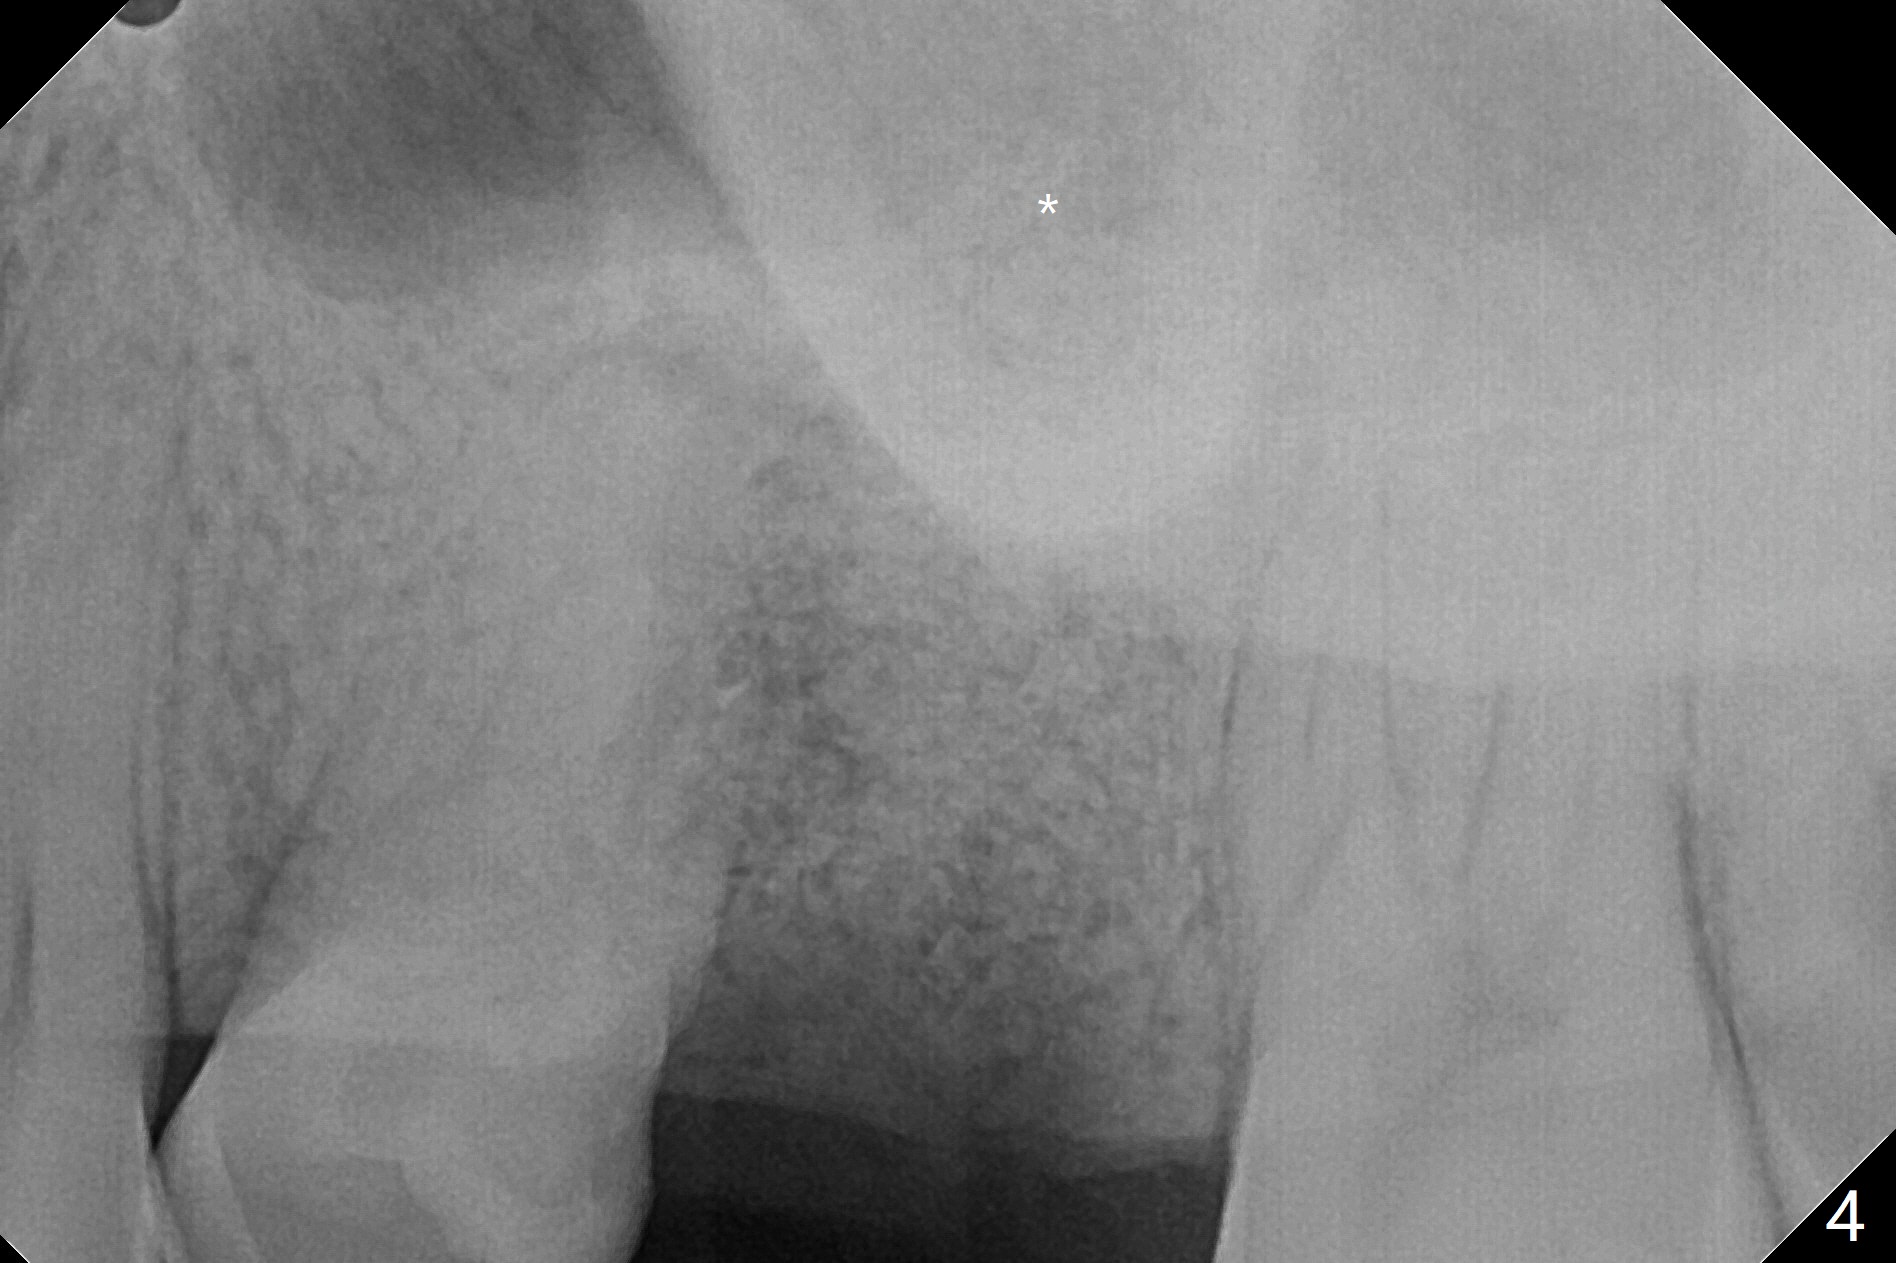

A 29-year-old man has pain in the upper left quadrant. It appears that the tooth #14 has endo and post failure with palatal fistula (Fig.1,2). The septum is almost non-existent; the palatal wall is low, while the sinus floor is present. Sticky bone is placed first against the defective palatal wall and presumably pushed as high as to the sinus floor (Fig.3-5). PRF plug/membrane and 6-month membrane are used to close the socket with 4-0 Chromic gut suture apparently securely, followed by periodontal dressing. Examination of the extracted tooth shows granulation tissue between the roots (Fig.6 *). Underneath the granulation tissue is cement-like material (Fig.7 C). Distal-to-mesial X-ray examination shows possible furcation perforation (Fig.8 *), while mesial-to-distal one the cement-like material in the furca and pulpal chamber as well as MB2 (Fig.9 >). The patient returns 8 days postop, reporting pain reduction, but wants to have #16 extracted. The periodontal dressing is loose, but stuck with 2 sutures underneath. When the dressing is removed, the wound looks normal (Fig.10). In fact the dressing is re-applied. The 6-month membrane has lost 1 month postop. The majority of the socket heals except the palatal (Fig.11 *), as related to the existing palatal fistula/defect (^). Orthodontics is being considered. If the buccal plate collapses 4.5 months post extraction, socket shield should have been done. In fact the buccal plate is robotic, while the bone density is low palatal in CT (Fig.12).